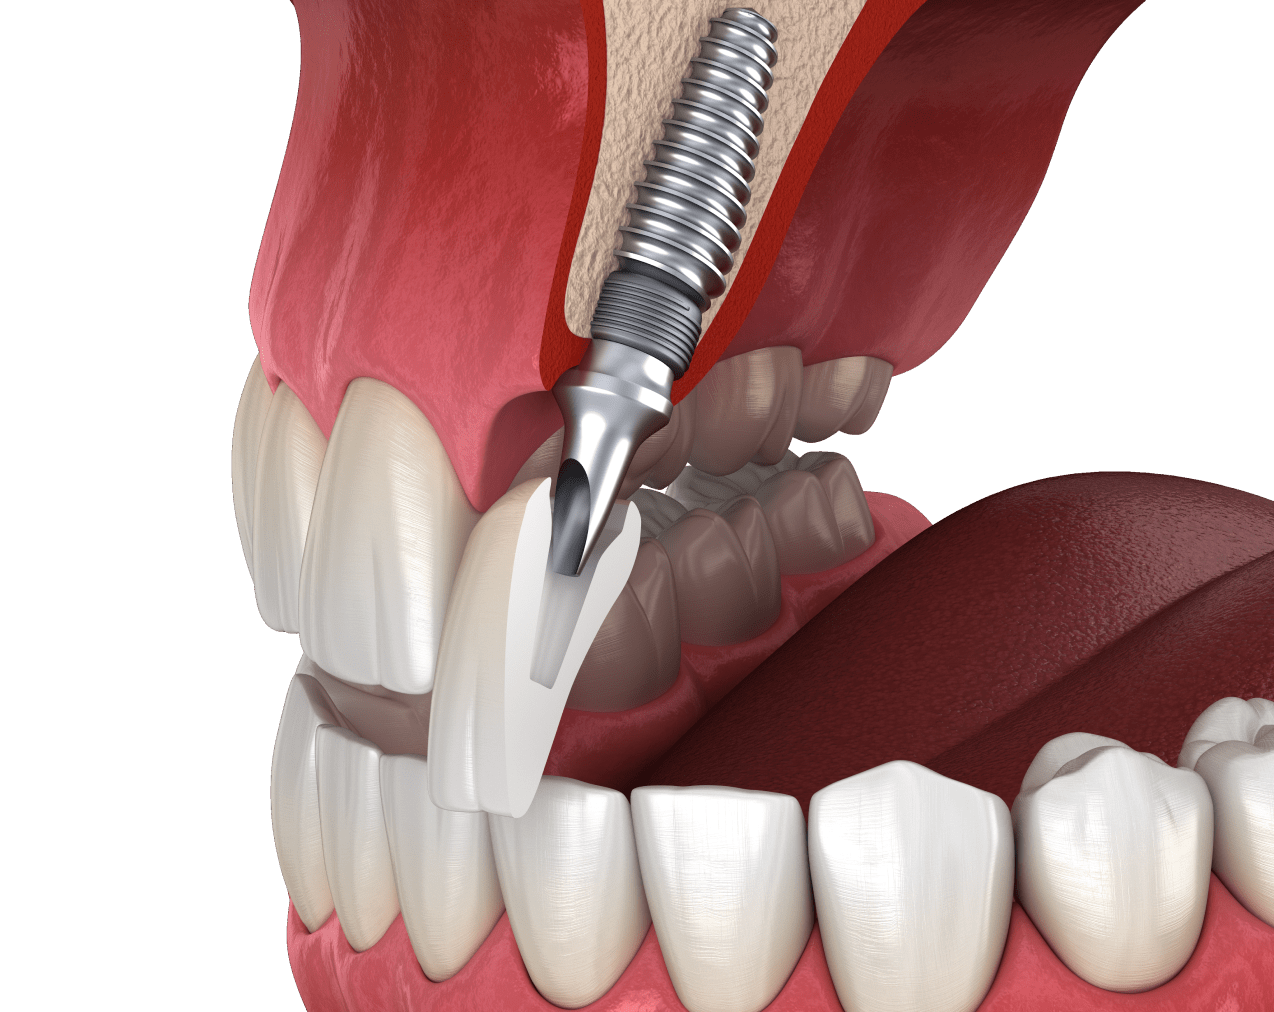

Імплантація зубів – це складне хірургічне втручання, яке потребує тривалого періоду реабілітації. Час приживлення імплантів є індивідуальним для кожного пацієнта. На термін відновлення тканин впливають безліч факторів, про які ми поговоримо далі.

Як довго приживаються зубні імпланти?

У стоматологічній практиці ЦІС зубний імплант у середньому приживається за 3-6 місяців.

При цьому приживлення титанового кореня на нижній щелепі відбувається швидше (2-4 місяці), а тканини на верхній щелепі гояться за 5-6 місяців. Це пов’язано з тим, що кістка на нижній щелепі щільніша, а кісткові тканини на верхній мають більш пухку структуру.